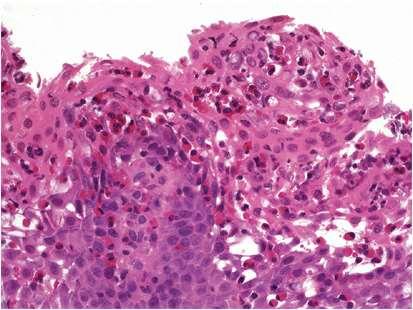

• 4. A 54 year old woman with multiple antral erosions: The biopsy shows a dense and diffuse lymphoid infiltrate in the lamina propria with infiltration of the glands by several aggregates of lymphocytes (lymphoepithelial lesions).

•.J Answer

• MALT lymphoma: Causes

Morphology (Centrocyte-like cells, LEL’s, plasma cell differentiation, Follicular colonisation)

Immunohistochemistry

• Other gastric lymphomas (DLBCL, mantle cell – multiple polyposis)